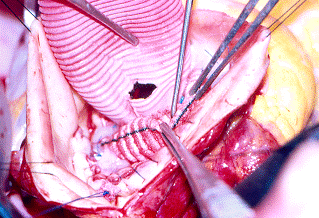

Tecnica di De Bakey e Cooley

Questa tecnica, realizzata nel 1956 da De Bakey e da Cooley, viene adoperata nei casi in cui l'aneurisma è localizzato all'aorta ascendente, con seni di Valsalva e valvola aortica normali, e prevede l'impiego di una protesi tubulare semplice di Dacron. Dopo aver cannulato l'arteria femorale o, se le condizioni lo permettono, l'aorta ascendente, una o due cannule venose vengono posizionate in atrio destro. Iniziata la CEC, la temperatura corporea del paziente viene portata a 25°C (ipotermia moderata), si clampa l'aorta ascendente prossimalmente al piede del tronco arterioso anonimo e si effettua la cardioplegia, cristalloide o ematica per via anterograda attraverso il bulbo aortico o gli osti coronarici e/o retrograda attraverso il seno coronarico. In caso di aorta calcifica "a porcellana", la CEC può essere eseguita in ipotermia profonda (18°C) ed arresto di circolo senza ricorrere necessariamente al clampaggio aortico.

La sacca aneurismatica, incisa longitudinalmente o asportata, viene sostituita da un tubo di Dacron, anastomizzato in termino-terminale sia prossimalmente che distalmente; rimosso il clamp aortico, ed effettuata una accurata purga dell'aria, si verifica la tenuta della protesi. Il paziente viene riscaldato progressivamente fino alla normotermia e, stabilizzata l'emodinamica, la CEC viene fermata.

sutura distale RISULTATO FINALE